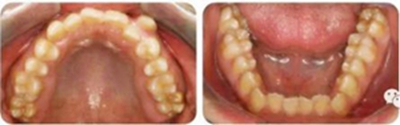

影像學(xué)檢查

無缺牙及多生牙,雙側(cè)下頜升支高度相等,智齒未萌。

頭影測(cè)量顯示為骨性Ⅲ類高角患者。